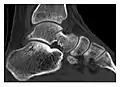

a

b

Figure 10: Calcaneal fatigue fracture in a 30-year-old male runner. Radiographs were normal (not shown). (a) Sagittal T1-weighted and (b) short tau inversion recovery images show a linear hypointensity (arrows) of calcaneal tuberosity within diffuse bone marrow edema, which appears as an ill-defined area of hyperintensity on a fluid sensitive pulse sequence (arrowheads).[1]